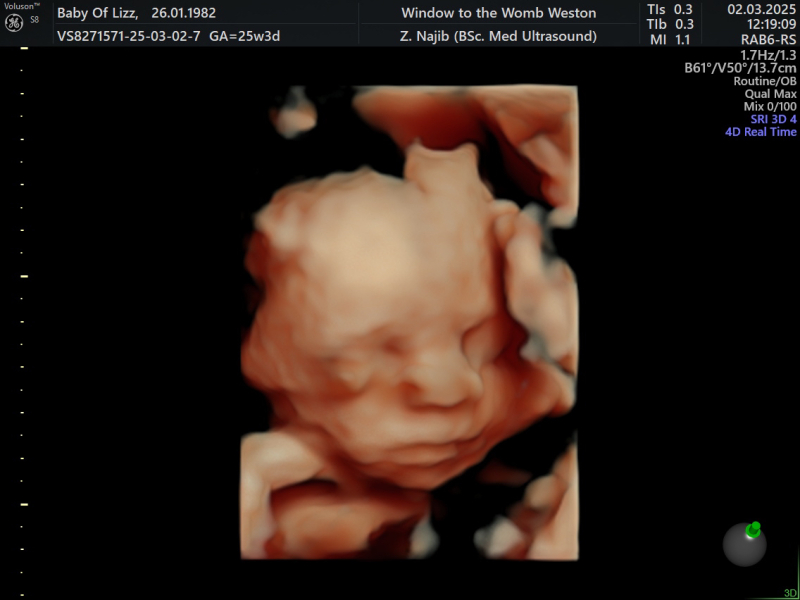

Had a cheeky 4D scan yesterday and am just obsessed at looking at its little face

Proper besotted ❤️

@DramaticFridge Gorgeous photo! And thanks re what you said about why they induce at 40 weeks, I couldn't remember exactly why she said they did!

In practically every scan I have had the baby has been reclining with its arm behind its head like it's just chilling out - but on this one it was grabbing its feet which was so lush to see!

Can't believe how much detail you can see on them! We were comparing it to a photo of my bf when he was a baby and it could be the same baby!